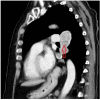

Figure 3

Figure 3. Invasion of the left inferior pulmonary vein with extension into the left atrium